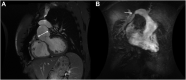

The arterial switch operation is the gold-standard treatment for dextro-transposition of the great arteries. Long-term follow-up data are beginning to reveal its natural history and associated late complications, including various reoperations for those complications. Given the unique anatomy and the increasing longevity of these patients, there is a need for effective surgical repair options to address aneurysmal and degenerative changes in both neoaortic and pulmonic roots. Thereby, we describe our technique and the novel considerations for prosthetic choice with reconstruction of both the neoaortic root and pulmonary artery, with satisfactory postoperative results.